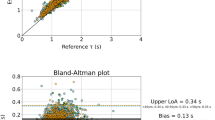

The value of k, derived by fitting aPWV and C T values, was 36.7 (95% CI: 36.2–37.2). Goodness of fit parameters were also calculated; the SSE was 29.94, the R 2 was 0.8 and the RMSE was 0.17. The value of k was also determined analytically according to Eq. (4) and it was found to be 39.4.

The fit curve for C T and aPWV values computed for the 1000 cases is illustrated in Fig. 2. Figure 3 shows the correlation between the total compliance and the predicted values of compliance via the fitted curve. The hemodynamic cases were divided into three subgroups based on the geometric change that was imposed in the arterial trees. The fit curves were also calculated for each of the three “arterial-size” subgroups and the k values were 32.8, 36.9 and 41.2 for the 10% decrease, control and +10% increase in arterial volume, respectively. Table 2 summarizes the fit results for all the curves.